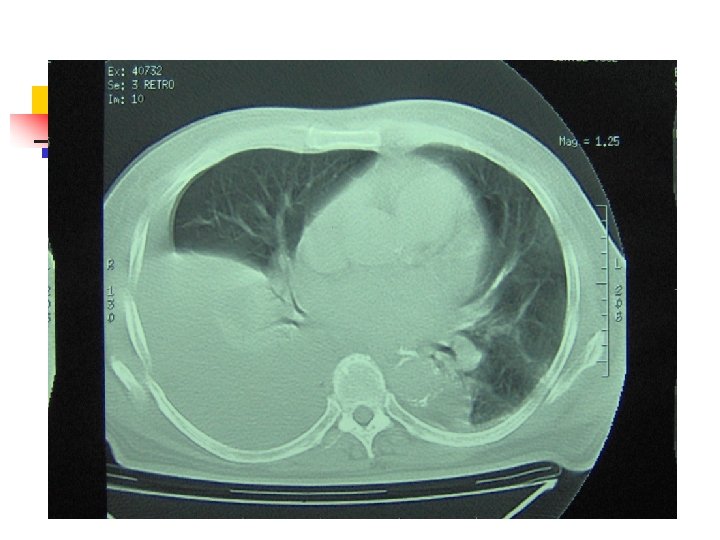

Aproximación diagnóstica: TAC Siempre TAC contraste n n Evaluar parénquima vecino Evaluación del mediastino. Desplazamiento contralateral Evaluación de DP tabicado Angio. TC Porcel JM, Light RW. Am Fam Physician 2006: 73: 1211

Broncofibroscopía Sospecha de neoplasia n Masa pulmonar en TAC o RX tórax n Derrame pleural masivo n Hemoptisis n Desplazamiento del mediastino hacia el lado del derrame Antunes G. Thorax 2003; 58: 29